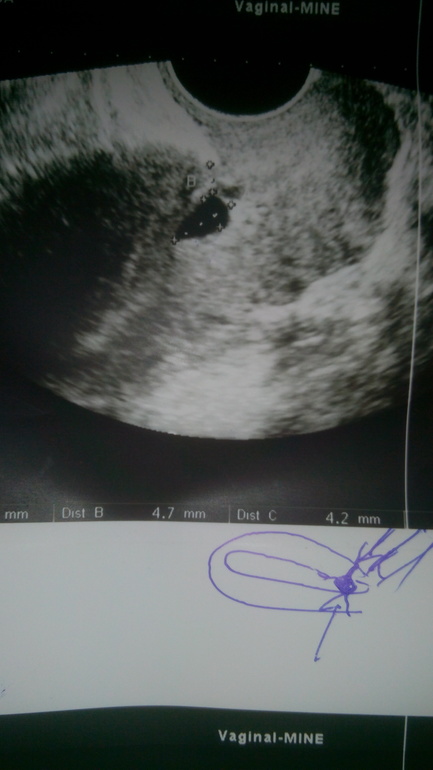

Второй врач на УЗИ ничего не увидел. М до сих пор нет. Тесты больше не делала.

Меня просто смущает то, что один врач увидел, а второй нет. Завтра пойду сдавать анализ на ХГЧ.

У меня со старшим на недели 4-5 тоже не видно было эмбриона, думали, что ЗБ, но тест показывал, что Б. А тут как-то странно.